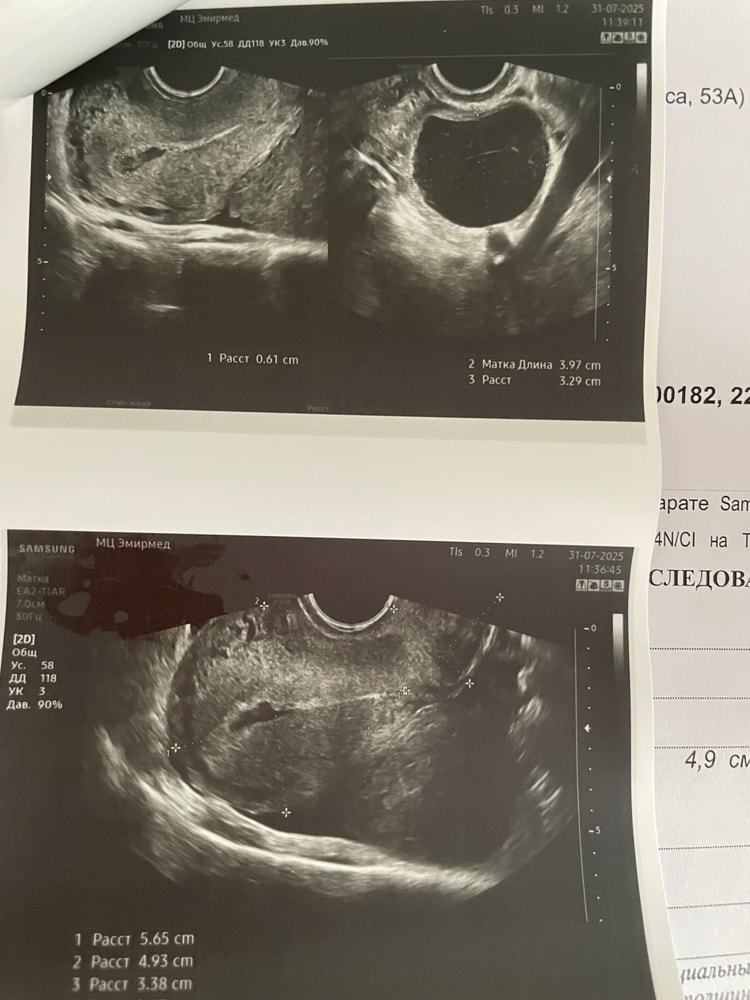

писала ранее, что был вакуум 25 июня (по мед направлению). Далее были остатки, кололи окситоцин, вроде все вышло, на узи было все отлично. Сегодня 31 июля, месячных нет. Тесты показывают вот так

Сходила на узи сегодня, врач сказала что в матке скорее всего сгустки, и с двух сторон кисты